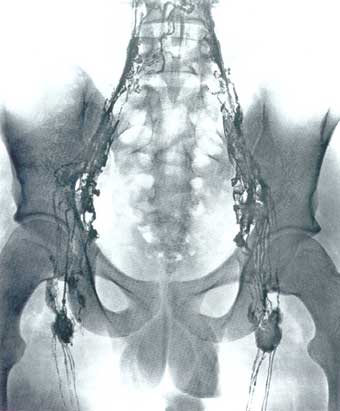

Image: a lymphangiogram of the inguinal and iliacal lymph ducts, lymph nodes and paravertebral anastomoses through ingestion of Lipiodol®. Image by Dr. L. Baumeister; Atlas der Anatomie des Menschen, Sobotta/Becher

Yet, it was known in the 1800s that vaccines clog our lymphatics and contain toxic materials which could lead to disease, even cancers. Even Jenner himself had trouble with his vaccines causing diseases, and death. He was nearly lynched in one town for his specious concoctions. Our lymphatic system is designed to carry our lymphocytes throughout our body and maintain control over our cellular immunity. Therefore, the injection of large molecular sized proteins (foreign tissues in the vaccines) will clog our lymph-nodes and create problems for the lymphatic system. Therefore, it is no mystery that vaccines and lymphatic diseases, like leukemias and lymphomas, are related.